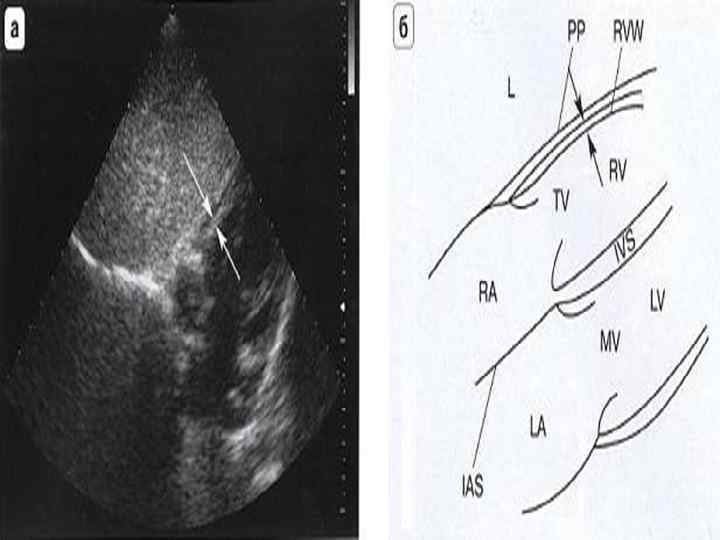

Ультразвуковая анатомия сердца В эхокардиографии используют ряд доступов к сердцу и магистральным сосудам: • Левый парастернальный • Апикальный • Субкостальный • Супрастернальный • Правый парастернальный